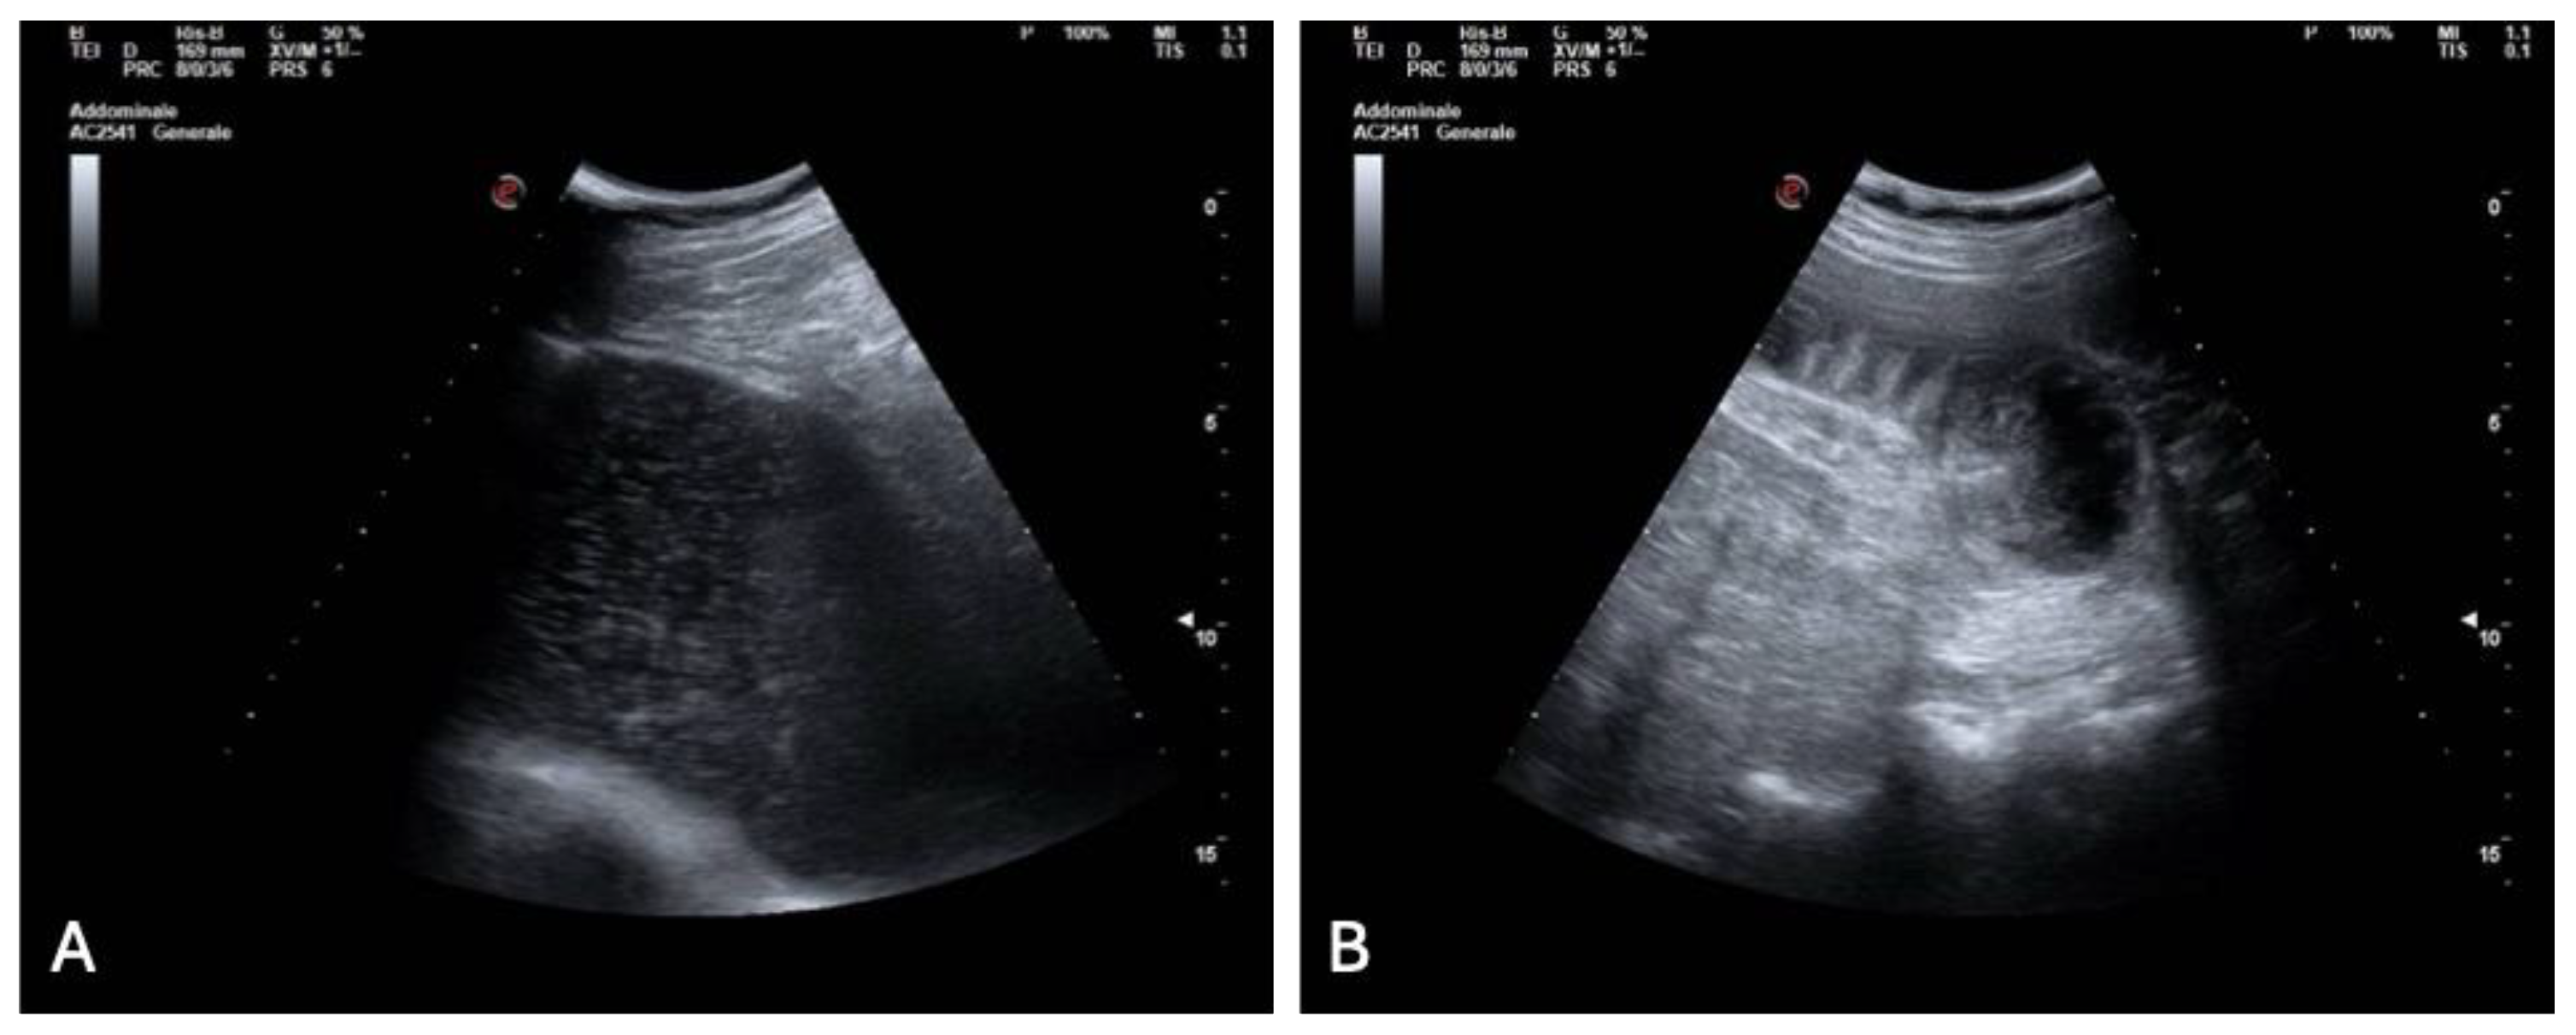

With the cardiac cause excluded, diagnostic attention shifted to the gastrointestinal tract. A bedside abdominal ultrasound demonstrated marked gastric distension and multiple dilated small bowel loops with reduced peristalsis and visible air–fluid levels, along with a suspected transition point (Figure 4 A, B).

Figure 4. Bedside abdominal ultrasound images: (A) markedly distended stomach; (B) multiple dilated small bowel loops with air–fluid levels and reduced peristalsis, suggestive of mechanical small bowel obstruction.